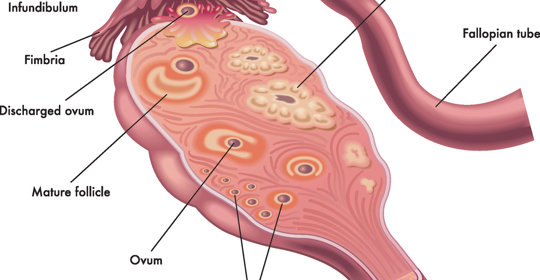

本文介紹了子宮頸糜爛與人類乳突病毒(HPV)(HPV)感染之間的關係以及子宮頸癌的一些常見症狀。子宮頸糜爛是子宮頸上皮細胞的一種病變,而HPV感染是導致子宮頸癌的主要原因之一。對於子宮頸糜爛患者來說,定期進行婦科檢查是非常重要的,可以早期發現並預防子宮頸癌的發生。同時,保持良好的個人衛生習慣也有助於減少HPV感染的風險。

子宮頸抹片檢查異常:處理流程與注意事項

子宮頸囊腫:臨床表現與處理原則

子宮頸水腫:診斷與治療方法

子宮頸炎:診斷方法、原因及治療